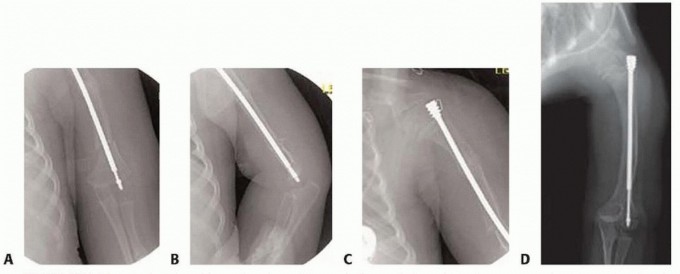

Tibial Technique

## Nails from the small bone set are used. These have a somewhat shorter female-threaded portion to avoid extension of the threads across the proximal tibial epiphysis.

## Injury to the anterior horn of the medial meniscus should be avoided, using an arthrotomy if necessary.

## A 0.62-inch K-wire is placed just lateral to the anterior horn of the medial meniscus and just anterior to the tibial spine in the non-weight-bearing surface. A soft tissue protector is helpful in directing the guidewire.

## A slight bend can be placed in the tip of the wire to assist in advancing wire if necessary. This usually places the wire in the midportion of the tibial epiphysis on the AP view and at the junction of the anterior and middle thirds on the lateral view.

## With the knee kept flexed in excess of 90 degrees, the guidewire is passed into the center position of the proximal metaphysis and shaft.

## Typically, the wire tends to go posteriorly and laterally so that the wire driver must be directed anteriorly and usually slightly medially.

## The guidewire is drilled down to the site of the first osteotomy, which often is the mid- to distal portion of the shaft of the tibia, although bowing of the proximal tibia also may be present.

## To perform the tibial osteotomy, a 1.5-cm incision is made. The periosteum is visualized and partially elevated. Multiple osteotomies may be necessary. However, in the vast majority of patients, a single incision with a segmental resection is preferable to multiple osteotomies (TECH FIG 6A).

## The key to the tibial osteotomy is to place the tibia in mild posterior bow to allow for anterior compression.

## Any residual anterior bow will lead to an increased risk of nonunion, progressive anterior bowing, and impede telescoping of the rod.

TECH FIG 6 • A. Incisions to correct tibial deformities. B,C. Note hole in male nail to allow locking with a wire if necessary. Correct placement of the distal male nail after complete correction of anterolateral bowing. D,E. Correct proximal tibial nail placement. F. Male nail cut in situ, which may require a more anterior entrance point, especially in smaller children, to accommodate the male nail cutter.

The guidewire is then passed beyond the osteotomy.

## Ideally, the entrance point to the distal tibial epiphysis is slightly posterior on the lateral view and slightly lateral on the AP view. This helps to avoid the tendency to valgus and anterior cutout.

## The male nail is either cut after determining the length with the C-arm before placement into the tibia or inserted, removed, and then cut after the appropriate length is determined (TECH FIG 6B-D).

## Alternatively, the rod can be placed in the standard fashion and cut in situ. However, this requires a somewhat more anterior entrance point to accommodate the male nail cutter.

## There is a small hole in the distal male nail to allow interlocking with a small K-wire, if additional stability is required. A blocking screw or wire may be used if absolutely necessary but frequently migrates and requires early removal.

## The female nail is cut to length in the same manner as for the femoral technique and inserted until the threaded portion is fully seated into the epiphysis.

## It usually is visible just a few millimeters deep to the articular cartilage, even when the C-arm suggests that the proximal nail is protruding into the joint (TECH FIG 6D,E).

## If the male nail is protruding above the female nail, as occurs with in situ cutting with the male nail cutter, it is vital to ensure that the knee will fully extend without impingement of the nail into the femur. With growth, the male nail will migrate distally in the female nail (TECH FIG 6F).